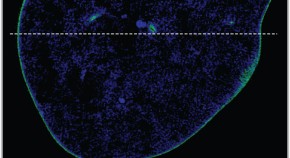

The 'death receptor' FAS regulates apoptosis of unwanted or dangerous cells, functioning as a guardian against autoimmunity and cancer development. Distinct cell types differ in the mechanisms by which FAS triggers apoptosis: in type I cells, FAS-induced activation of caspase-8 suffices for cell killing, whereas in type II cells there must be caspase cascade amplification. Here it is shown that the inhibitor of apoptosis XIAP is the critical factor determining this — without it, a type II cell dies in the same way as a type I cell.